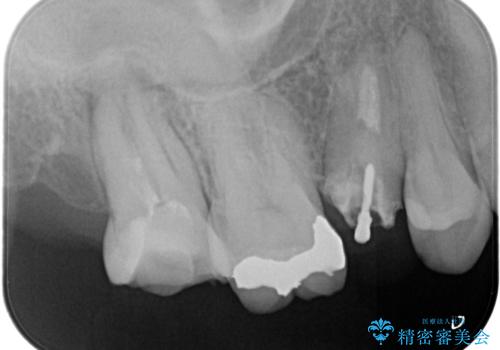

セラミッククラウンによる奥歯の修復

担当医 河口智英